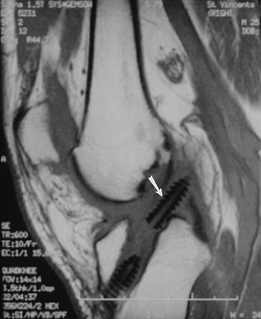

FIGURE 5-1

Patellar view demonstrating subluxation after reduction of a patellar dislocation. There is a displaced osteochondral fragment (arrow) laterally. |